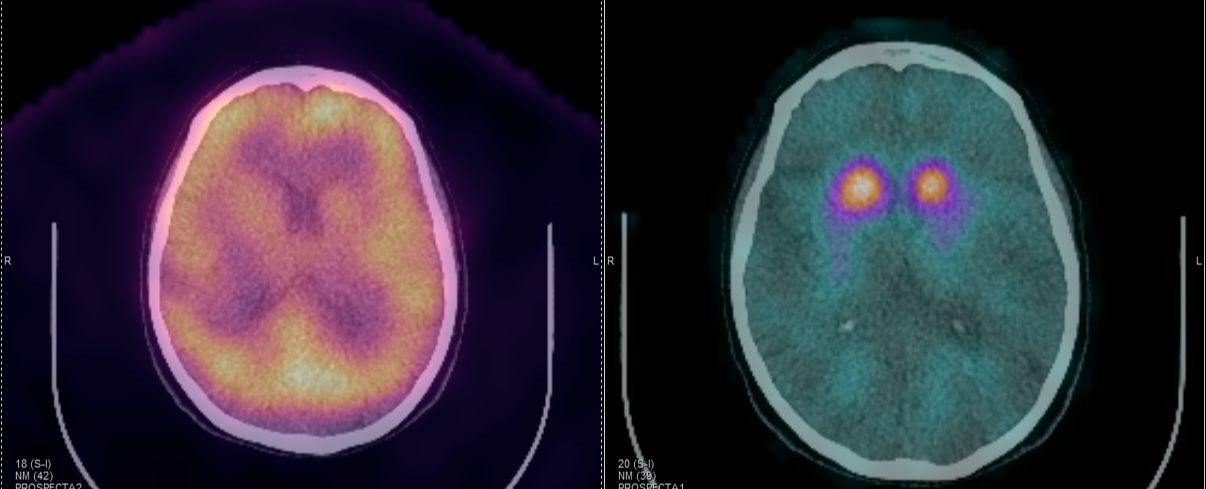

Το Lu-177 PSMA αποτελεί μια στοχευμένη ραδιονουκλιδική θεραπεία για ασθενείς με ορμονοάντοχο μεταστατικό καρκίνο του προστάτη (mCRPC), αξιοποιώντας τη υπερέκφραση του PSMA (Prostate-Specific Membrane Antigen) στα καρκινικά κύτταρα. Προηγείται PSMA PET/CT για ακριβή χαρτογράφηση της νόσου και επιβεβαίωση επαρκούς πρόσληψης του ραδιοφάρμακου. Το Lu-177 PSMA συνδέεται στους PSMA-υποδοχείς, επιτρέποντας στοχευμένη ακτινική δράση υψηλής κυτταροτοξικότητας σε μεταστατικές εστίες οστών και μαλακών μορίων. Η χρήση εξειδικευμένων δοσιμετρικών εργαλείων επιτρέπει την ποσοτική αποτίμηση της δόσης σε κρίσιμα όργανα (π.χ. σιελογόνοι αδένες, νεφροί, μυελός) και στον όγκο, συμβάλλοντας σε εξατομικευμένη θεραπευτική προσέγγιση. Μετά από κάθε κύκλο πραγματοποιείται PSMA PET/CT ή FDG PET/CT (όπου ενδείκνυται), καθώς και στενός αιματολογικός έλεγχος για αξιολόγηση της ανταπόκρισης και των πιθανών τοξικοτήτων. Η θεραπεία έχει αποδειχθεί ιδιαίτερα αποτελεσματική στη μείωση του καρκινικού φορτίου, στη βελτίωση του πόνου, στη μείωση των επιπέδων PSA και στη σημαντική παράταση του προσδόκιμου επιβίωσης σε ασθενείς με εκτεταμένη και ανθεκτική νόσο.

Με τη SPECT‑CT ποσοτικοποίηση υπολογίζουμε απορροφούμενες δόσεις σε όγκους και όργανα‑στόχους (νεφροί, σιελογόνοι, ήπαρ, μυελός κ.ά.). Αυτό: